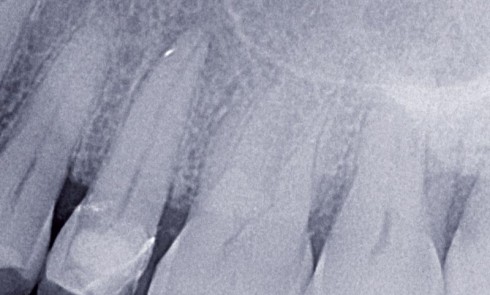

Article réservé à nos abonnés Préservation du parodonte impacts innovants du tout céramique au numérique

Depuis de nombreuses années, les problèmes inhérents au couple parodonte-prothèse font débat et sont l’objet de multiples publications. In vitro...